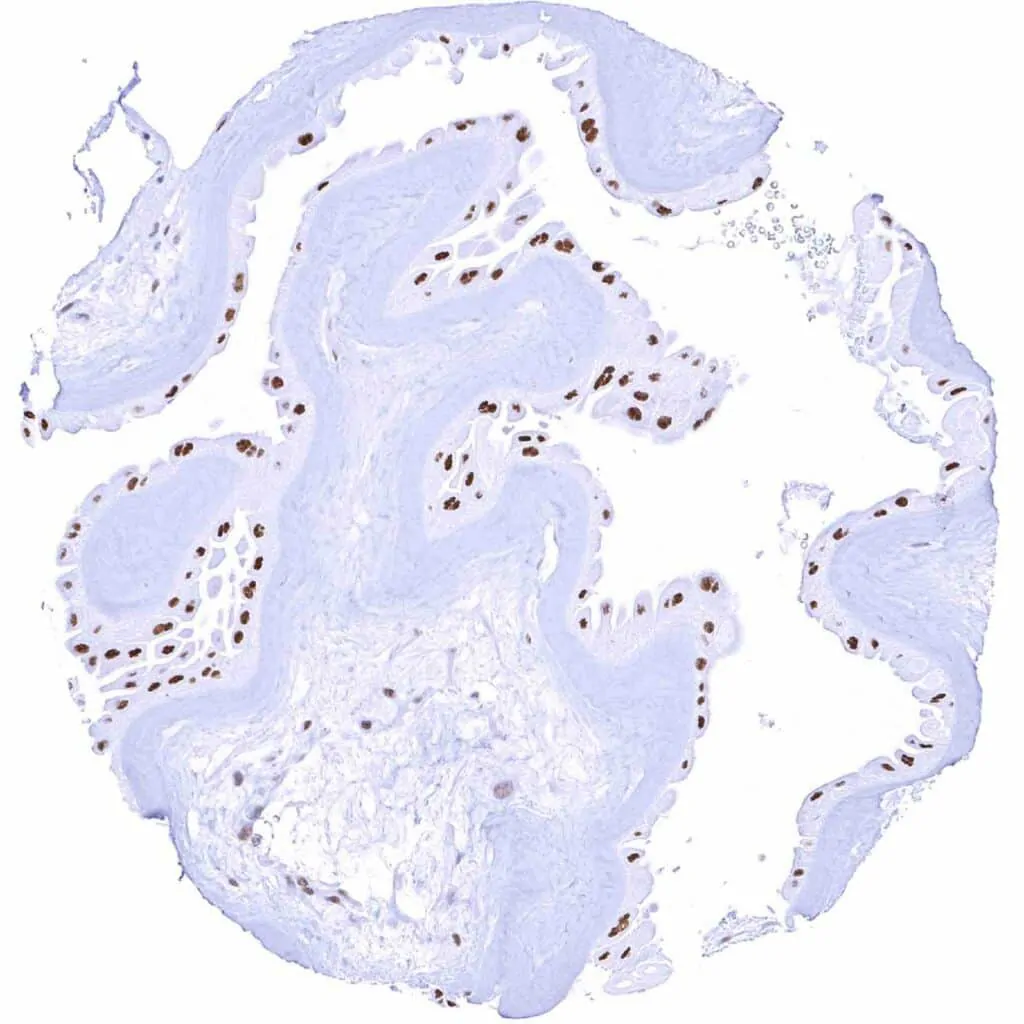

Uterus, ectocervix – Moderate TLE1 staining of squamous epithelial cells, predominantly of the suprabasal cell layers